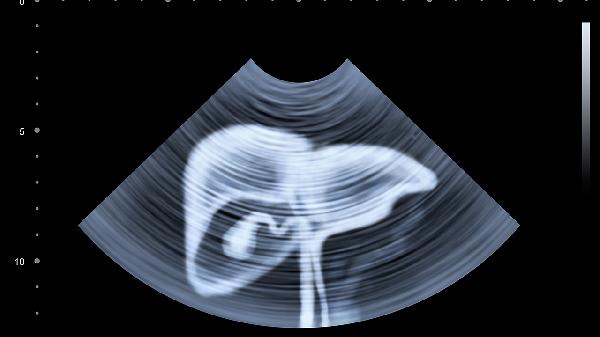

腸易激綜合征、慢性胃炎等疾病常伴隨腹脹癥狀,可能與腸道敏感度增高或炎癥反應(yīng)有關(guān)。若脹氣持續(xù)超過兩周,或伴隨體重下降、血便等警示癥狀,需及時進行胃腸鏡檢查。